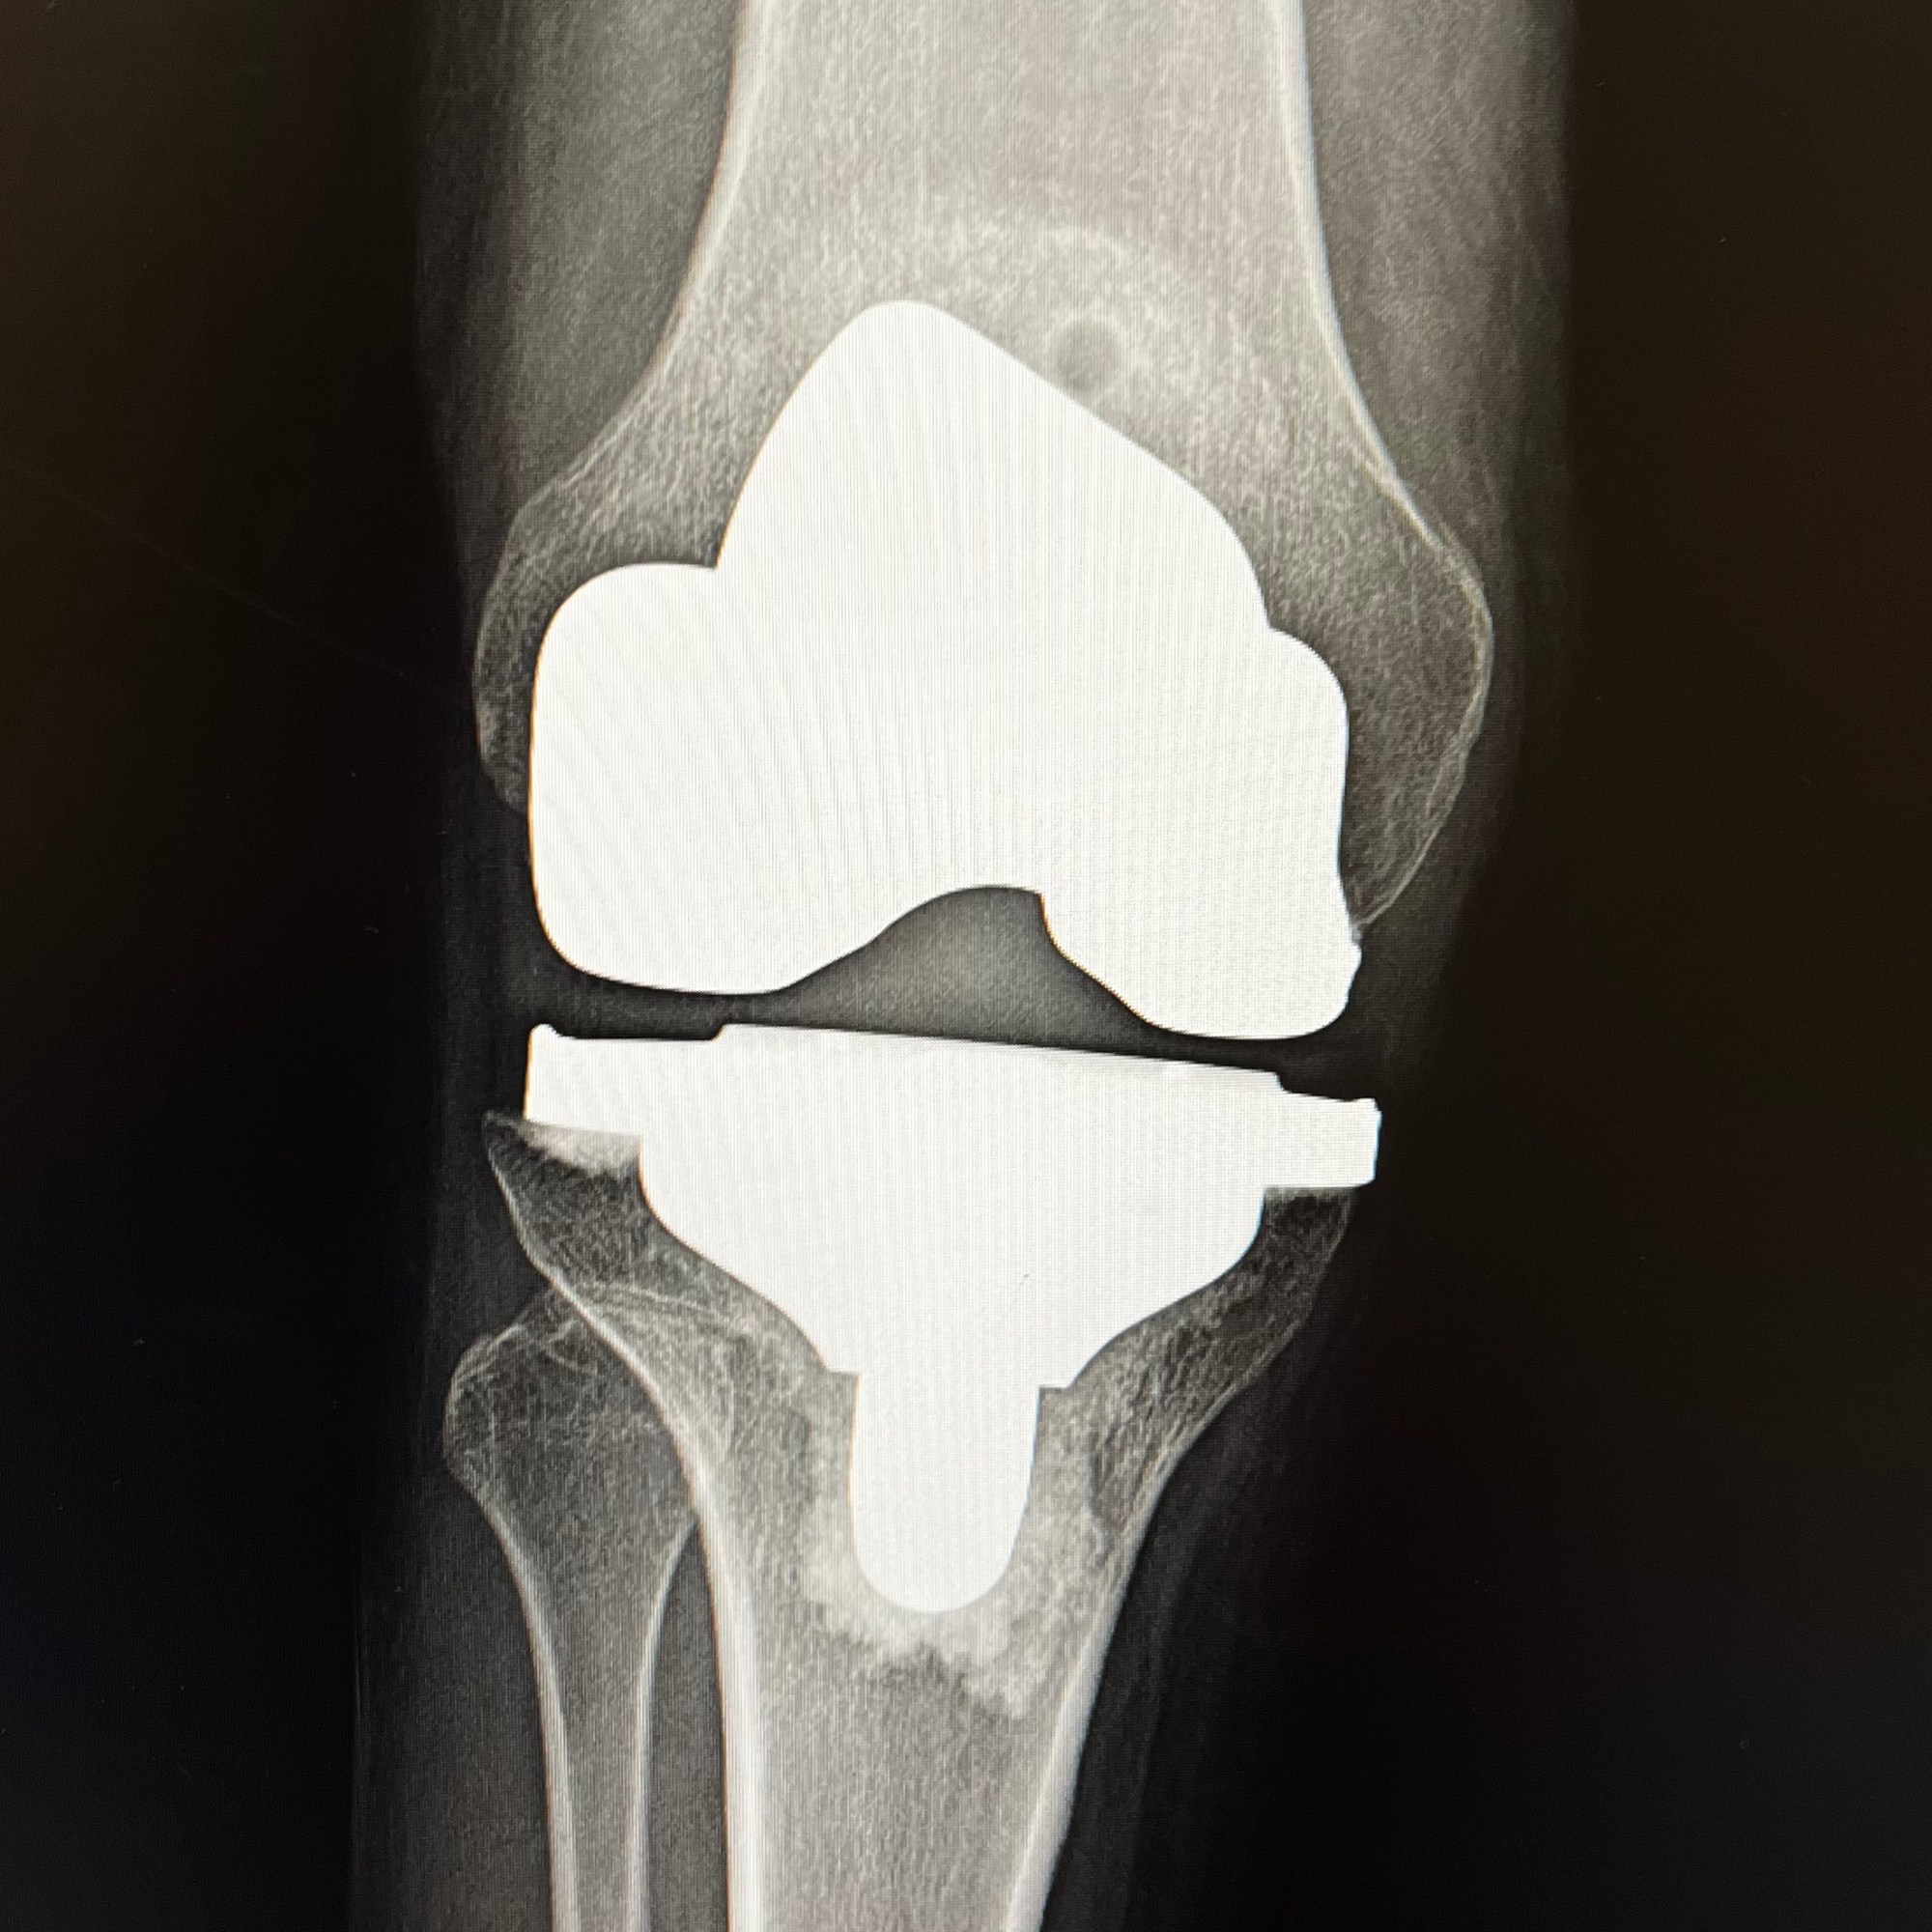

In May (just as Diane Hiller, medical intuitive had predicted) I had my 6th joint replacement/12th surgery (not including two c-sections); for the injured knee that had been “loose” since I was a kid. It had finally begun to really hurt and made stairs or any amount of standing/walking vey painful. When it came time to have it done, I went to one of the best orthopedic surgeons — Dr. Perry Green. I had met Dr. Green 22 years ago when he performed my very first joint replacement in 1999 — my left hip shown here, which is still going strong to this day! You can also see my Lower Lumber Fusion – 2010 also going strong!

The operation went perfect. I had a nerve block so that my entire leg was pretty numb for the first 24 hours or so resulting in minimal pain. I stayed in the hospital one night and recuperated at home. The hospital sent a Physical Therapist to my home for the first week to teach me the various exercises to ensure my knee did not stiffen up. I did my exercises diligently and eventually made a full recovery with wonderful range of motion and almost no pain! Once the incision was fully closed, I applied my THC/CBD cream which helped with post-surgical pain and scar healing. Now, the incision is barely noticeable. I’m able to walk and do stairs without any pain now. However, after being active for a while, it starts to swell a bit and gets a little achy. Just my reminder to sit down and take it easy!